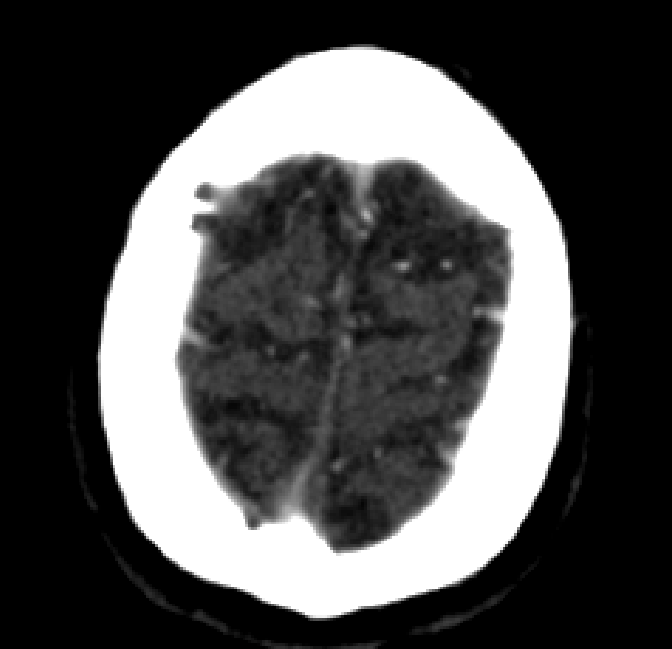

Refer to caption

Figure 4.3: Segmentation on internal carotid arteries. Unaltered image (left). No pretrain model (mid-left). Fine-tuned model (mid-right). Hand-labeled ground truth (right).